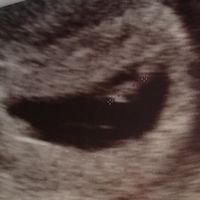

Buonasera a tutte..... Ho saputo di essere in cinta da due settimane ho fatto la prima eco alla quinta settimana+5 però il cuore del bambino non si sente ho fatto la prima beta ed era 18650 lunedì la rifaccio a chi è successo e come è andata a...